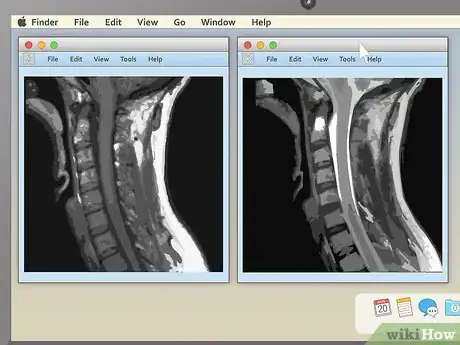

3Pick an appealing series layout. MRI programs almost always have the ability to display more than one image at once. This makes it convenient for doctors to compare different views of the same area or even MRIs taken at different times. For most non-doctors, it's easiest to simply choose a one-image-at-a-time layout and cycle through the images individually. However, there should be onscreen instructions to show two, four, or many more images at once, so feel free to play around with this feature.

- For example, if you're viewing a sagittal image of your spine along with a cross section of one of your vertebrae, moving the section-cut line may allow you to cycle up and down through the various vertebrae above and below it. This can be useful for locating problems like herniated discs.

2Examine the structure of the vertebrae for spinal MRIs. MRIs of the spine are typically some of the easiest for non-doctors to read (especially in sagittal view). Look for noticeable misalignments in the vertebrae or fluid discs. Having just one of either be out of alignment (as in the example above) can be the source of serious pain.

- Behind the spinal vertebrae, in sagittal view, you'll see a white, rope-like structure. This is the spinal cord, the structure connected to all the body's nerves. Look for spots where the vertebrae or discs seem to "pinch" or press into the spinal cord — because the nerves are so sensitive, just a little pressure can lead to pain.